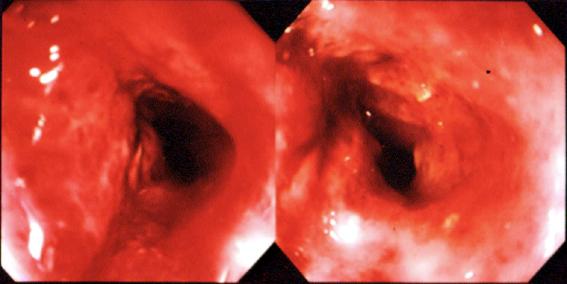

clasificación del pacienteTumor Epitelial Maligno/Adenocarcinoma

parte(separada por órganos)colon/transverso

método de exámenEndoscopia

clasificación ectoscópica de tumoresTipo 4(Tipo difusamente infiltrado)/

diámetro mayor del tumor40 -

grado de penetracións(a)